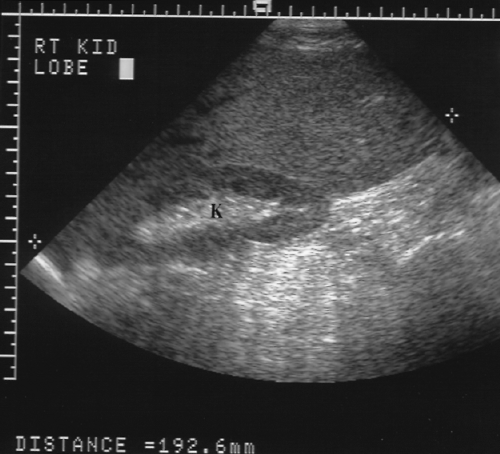

Riedel's Right Hepatic Lobe

Riedel's Right Hepatic Lobe. The probe is angled cephalad under the ribs to avoid any bowel or ribs shadowing over the liver. Over time, the thyroid may enlarge, forming a painless goiter. Some people eventually develop hypothyroidism with accompanying weight gain, fatigue, constipation, depression, hair loss. Known manifestations include retroperitoneal fibrosis, mediastinal fibrosis and riedel's thyroiditis. The liver is the largest organ in the human body.